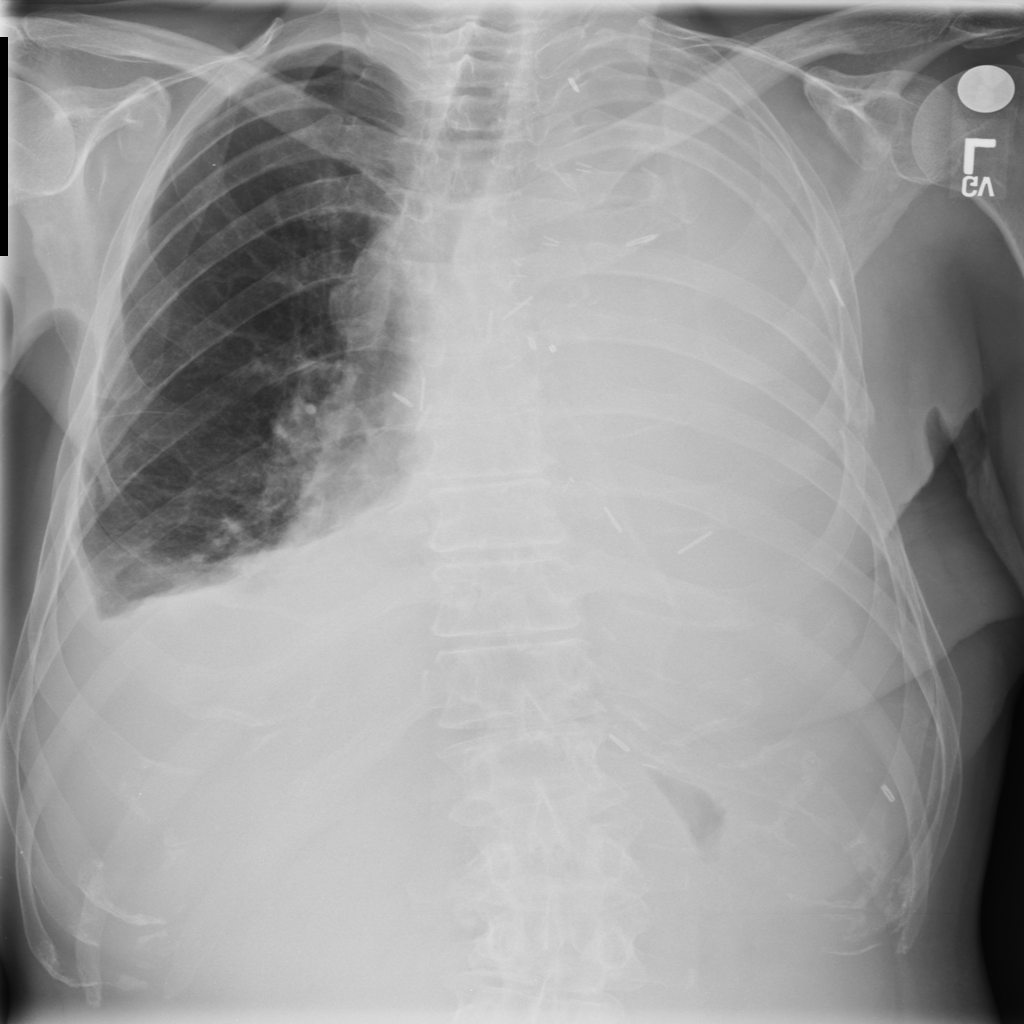

PAT-2F67 · IMG-000Effusion

PAT-2F67 · IMG-000

PA